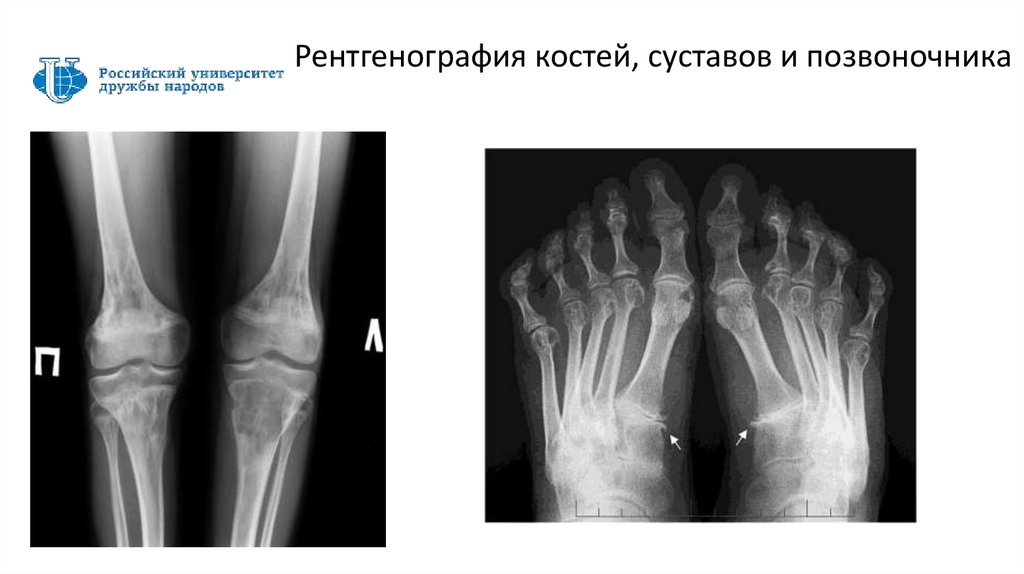

Рентгенография костей, суставов и позвоночника

51

Текст набирается шрифтом Trebuchet от 16 кегля

53